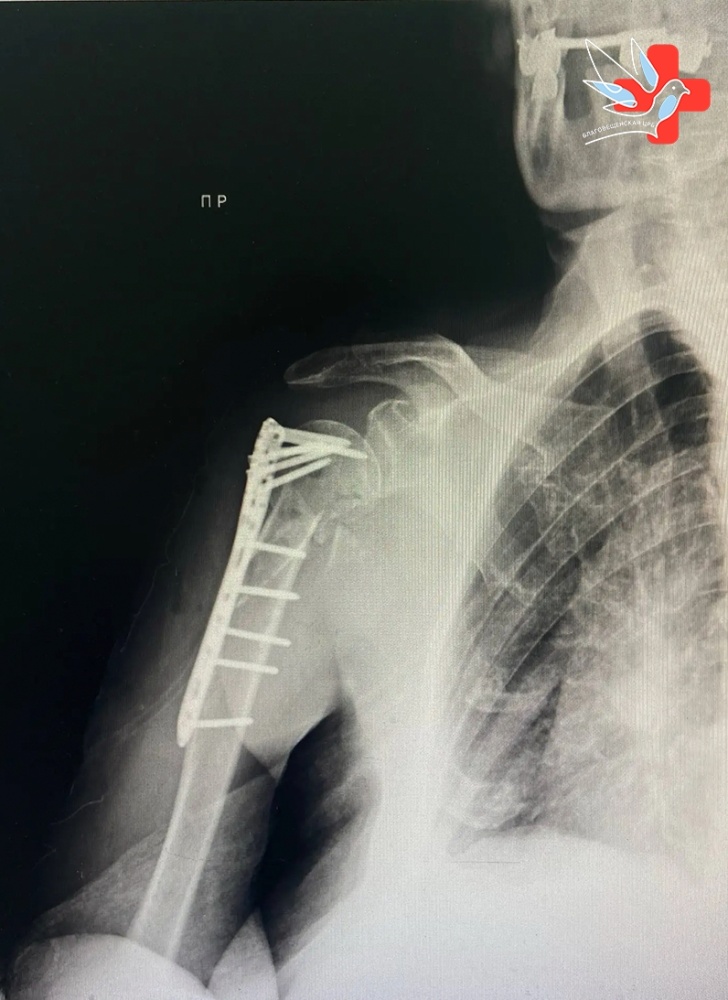

Врач-травматолог Сараж Багаутдинович Измайлов успешно провёл сложную операцию — остеосинтез с применением титановой пластины. Благодаря профессионализму доктора и слаженной работе медицинского персонала, пациентка уже выписана домой с положительной динамикой.